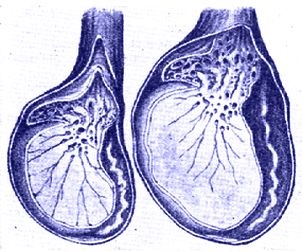

Pentru a înțelege motivul pentru reducerea testicule la bărbați, este important să se înțeleagă anatomia testicule. Fiecare ou este compus din două tipuri de celule: celule germinale și a celulelor Leydig (Leydig).

În condiții normale, sănătoase de sex masculin produce ambele tipuri de celule, în proporții egale, forțând testiculele să fie rotundă, stabilă și completă. În caz de reducere a testiculelor la bărbați de la oricare dintre aceste tipuri de celule sau, în unele cazuri, ambele tipuri încep să moară, provocând fluctuații ale nivelului de lichid. Această schimbare de fluid contribuie la surpare a scrotului, testiculele sunt foarte moi și sunt într-o stare liberă.